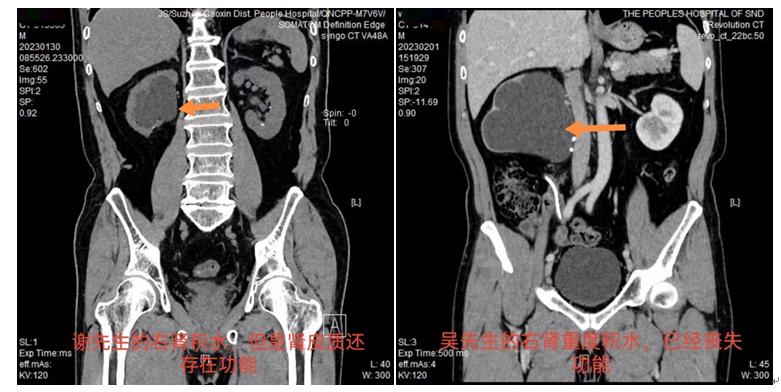

谢先生是输尿管狭窄合并输尿管结石的患者,一年前行输尿管结石钬激光碎石术,术后留置输尿管支架管引流,术后定期随诊,肾积水一直改善不明显,于近期在我院泌尿外科行腹腔镜下输尿管狭窄段切除+吻合术,术后谢先生恢复良好,由于谢先生平时比较重视,定期复查,处理得比较及时,积水的肾脏得到了及时处理及保留。

同样是肾积水,患者吴先生治疗结果就不同了。4年前,因为输尿管结石行输尿管镜下钬激光碎石手术,术后由于工作繁忙及自身大意,未按照医嘱定期复查,最后由于长期肾积水导致血压升高才到我院进行检查,检查时发现输尿管狭窄,患侧肾积水已经非常严重,影像检查肾脏皮质菲薄,患肾失去功能,最后不得不行腹腔镜下无功能肾切除术。